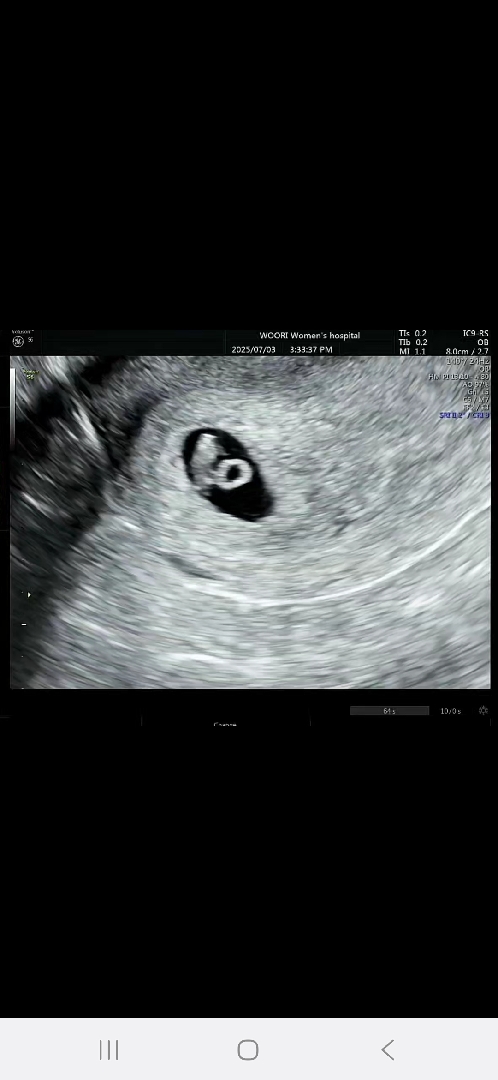

7주1일 심소듣고왔어요!!!

난황도 너무이쁘죠?? 벌써부터 도치맘인거같네요ㅎㅎ 작년 떠나보낸적있어 병원을 아에늦게가서 원큐(아기집/난황/심소)한번에 확인하고싶어 어제갔는데 오늘로써 7주2일차 딱풀이입니다 심소 148나왔는데 건강하죠~?^^